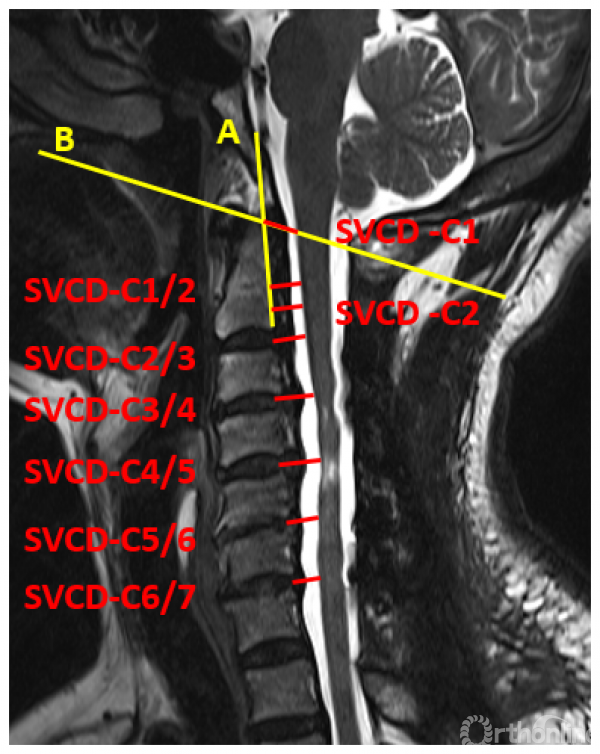

在本研究中,我们增加了不同减压范围的组别。对129例接受了颈后路减压手术且减压充分的患者的资料进行回顾研究,并且根据减压范围分为:C4-7组(n=11),C3-6组(n=61),C3-7组(n=32),C2-7组(n=25)。以后路术后椎髓间距(Vertebral body-Cord Distance, VCD)作为代表减压限度的参数:后路减压术后椎体后缘连线上各点至脊髓前缘的距离(图1)。

图1 椎髓间距(VCD)的测量

于是,我们回顾性分析了45例含上颈椎后路减压的压迫性颈脊髓病患者的临床资料,按减压范围分为C2-7组(25例)和C1-7组(20例)。利用本系列研究第三部分建立的方法,对两组各个节段的椎髓间距(VCD)进行测量和比较。与之前的研究不同的是,为了避免由于上颈椎形态不规则对测量造成的影响,将参数测量方法人为的标准化,称为标准化椎髓间距(standardized vertebral -cord distance, SVCD),并对测量位点进行了细化,增加了寰椎水平的数据(记为SVCD-C1)、枢椎齿突与枢椎椎体结合部的数据(记为SVCD-C1/2)、枢椎椎体中部水平的数据(记为SVCD-C2)(图1)。并对各个节段的SVCD进行组间比较。

图1